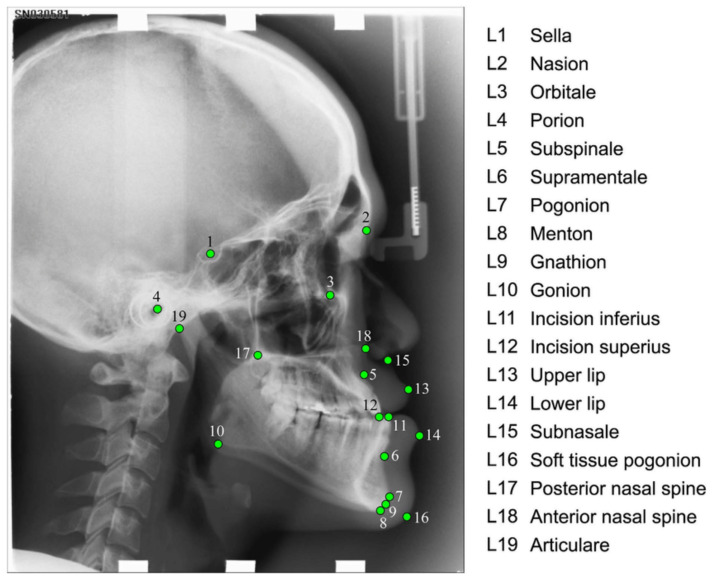

阻塞性睡眠呼吸暂停(OSA)是一种影响成人和儿童的常见疾病。其特点是反复发作呼吸暂停(呼吸停止)和呼吸减弱(呼吸减少),导致间歇性缺氧。我们认识到有小儿和成人 OSA,本文主要讨论小儿 OSA。成人经常白天嗜睡,而儿童更容易出现行为异常。早期诊断和治疗对于防止儿童发育受到负面影响非常重要。如果不进行治疗,儿童患高血压或其他心脏问题的风险可能会增加。诊断 OSA 的黄金标准是在睡眠中心进行多导睡眠图(睡眠检查)PSG。这种检查不仅费用昂贵,而且会给患者带来很大压力,尤其是对儿童而言。患者必须在睡眠中心过夜。因此,筛查工具非常重要。多项研究表明,OSA 筛查工具可以基于面部解剖地标。解剖地标是位于特定解剖位置的地标。为了筛查工具的目的,需要确定一个特定的解剖位置列表。我们将介绍一项关于自动识别患者头部三维扫描图像上这些地标的调查研究。我们正在考虑和比较基于知识的识别技术和基于人工智能的识别技术,重点是开发自动 OSA 筛查工具。

Obstructive Sleep Apnea (OSA) is a common disorder affecting both adults and children. It is characterized by repeated episodes of apnea (stopped breathing) and hypopnea (reduced breathing), which result in intermittent hypoxia. We recognize pediatric and adult OSA, and this paper focuses on pediatric OSA. While adults often suffer from daytime sleepiness, children are more likely to develop behavioral abnormalities. Early diagnosis and treatment are important to prevent negative effects on children's development. Without the treatment, children may be at increased risk of developing high blood pressure or other heart problems. The gold standard for OSA diagnosis is the polysomnography (sleep study) PSG performed at a sleep center. Not only is it an expensive procedure, but it can also be very stressful, especially for children. Patients have to stay at the sleep center during the night. Therefore, screening tools are very important. Multiple studies have shown that OSA screening tools can be based on facial anatomical landmarks. Anatomical landmarks are landmarks located at specific anatomical locations. For the purpose of the screening tool, a specific list of anatomical locations needs to be identified. We are presenting a survey study of the automatic identification of these landmarks on 3D scans of the patient's head. We are considering and comparing both knowledge-based and AI-based identification techniques, with a focus on the development of the automatic OSA screening tool.